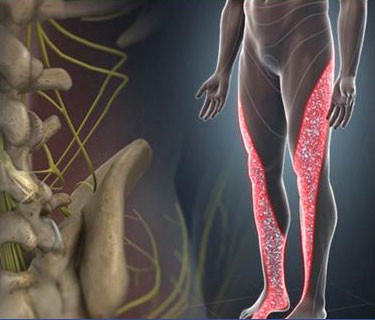

Neck pain is a frequent issue for people affected by poor posture. It can also stem from overuse, wear and tear, injury, and many other potential factors. It can be challenging to recover from intense neck pain without the right professional help. We offer pain management and treatment options that can help to make life enjoyable and pain free once again.